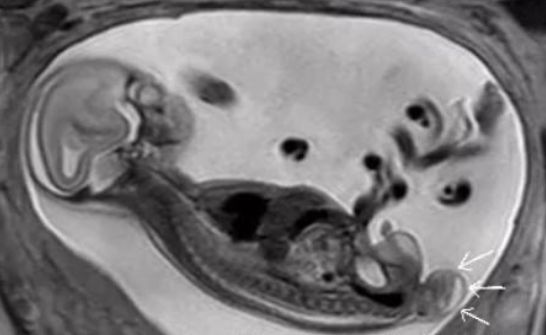

▲鄭姓女子在產檢時,發現胎兒脊柱有異常。(圖/翻攝自網易新聞,下同)

大陸一名鄭姓女子懷孕5個月時,到醫院產檢發現胎兒的屁股位置鼓起一個包,看起來就像條尾巴,讓夫妻倆不知該如何是好。經廈門大學附屬第一醫院診斷,初步判定為胎兒骶尾部畸胎瘤,決定實施介入性產前羊水穿刺,評估胎兒的腫瘤為良性後,建議孕婦繼續妊娠,最後平安生下寶寶,母子均安。

鄭女和家屬聽從了姜金娜主任醫師的建議,實行了介入性產前診斷羊水穿刺;檢驗科細胞遺傳學專家邱惠國副主任技師,為寶寶的羊水進行了染色體核型檢測,結果正常。由於寶寶屬於胎兒骶尾部畸胎瘤(I型),80%預後良好,勇敢的父母選擇繼續妊娠。

▲畸胎瘤是小兒常見實體瘤之一。

隨著寶寶一天天發育長大,畸胎瘤也在長大,幸運的是沒有出現宮內併發症,生長指標在正常範圍內。懷孕38週時,醫生為鄭女做了剖宮產手術,手術順利,術後直接轉至新生兒科病房。寶寶出生後第3天,兒外科團隊為寶寶進行了手術,手術很成功,且確認腫瘤為良性,目前寶寶已經1歲,生長發育一切正常。

據了解,畸胎瘤是小兒常見實體瘤之一,好發在身體中線及其兩旁,由三胚葉組織構成,其中又以骶尾部畸胎瘤最多見,它可發生在任何年齡,以新生兒及嬰兒期最多見。隨著產前篩檢技術發展,骶尾部畸胎瘤的產前診斷率可達90%以上,其病理性質有良惡性之分,絕大多數新生兒骶尾部畸胎瘤為良性腫瘤。